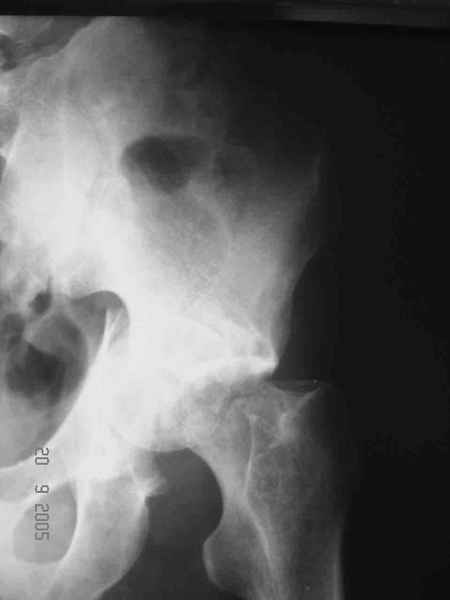

Контрольный снимок перед разрешением нагрузки прямой 13/10/03

|

Больной 18 мая 2003 года в автоаварии получил перелом левой вертлужной впадины, вывих бедра. Госпитализирован в один из стационаров области.Вывих вправлен. В последствии бедро вывихивалось еще дважды. На консультацию был представлен снимок от 19.05.03г., больной переведен к нам 3.06.03г. Снимок при поступлении - перелом впадины, задне-верхний вывих бедра. 05.06.2003 г. выполнено открытое вправление вывиха левого бедра и остеосинтез стенки вертлужной впадины двумя винтами. Послеоперационный период без осложнений. Объем движений в левом тазобедренном суставе восстановился полностью. Выписан на амбулаторное лечение в удовлетворительном состоянии с рекомендациями 3 месяца ходить на костылях без нагрузки на оперированную конечность. На контрольных рентгенограммах левого тазобедренного сустава 13.10.2003 г. - признаки консолидации перелома; плотность, форма головки и состояние суставных поверхностей удовлетворительные. Разрешена дозированная осевая нагрузка, на конечность с использованием дополнительной опоры. 19.12.2003 г. больной обратился с жалобами на боли в левом тазобедренном суставе. На рентгенограммах левого тазобедренного сустава 19.12.2003 г., 20.02.04г. - асептичекий некроз головки бедра. 5.04.04г. - эндопротез. Сейчас ходит без трости, не хромает. Особенность эндопротезирования - при удалении винтов прослежена линия перелома заднего края впадины и предложено установить чашку несколько меньшего диаметра, чтобы она была покрыта несломанной частью.